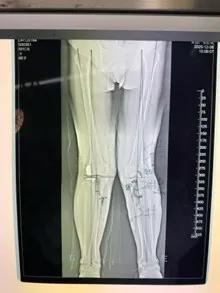

經(jīng)過詳細(xì)的體格檢查、影像學(xué)評(píng)估和三維重建,醫(yī)療團(tuán)隊(duì)確認(rèn)鮑奶奶的情況非常適合進(jìn)行膝外側(cè)單髁置換術(shù)。這種微創(chuàng)手術(shù)創(chuàng)傷小、恢復(fù)快,能夠最大程度保留膝關(guān)節(jié)的自然結(jié)構(gòu)和功能。

手術(shù)當(dāng)天,骨科團(tuán)隊(duì)采用微創(chuàng)切口,僅約8厘米,遠(yuǎn)小于傳統(tǒng)全膝關(guān)節(jié)置換手術(shù)切口。術(shù)中精準(zhǔn)定位,僅置換病變的膝關(guān)節(jié)外側(cè)間室。

整個(gè)手術(shù)過程僅持續(xù)約1小時(shí),術(shù)中出血不到100毫升。術(shù)后鮑奶奶被送回病房,生命體征平穩(wěn)。